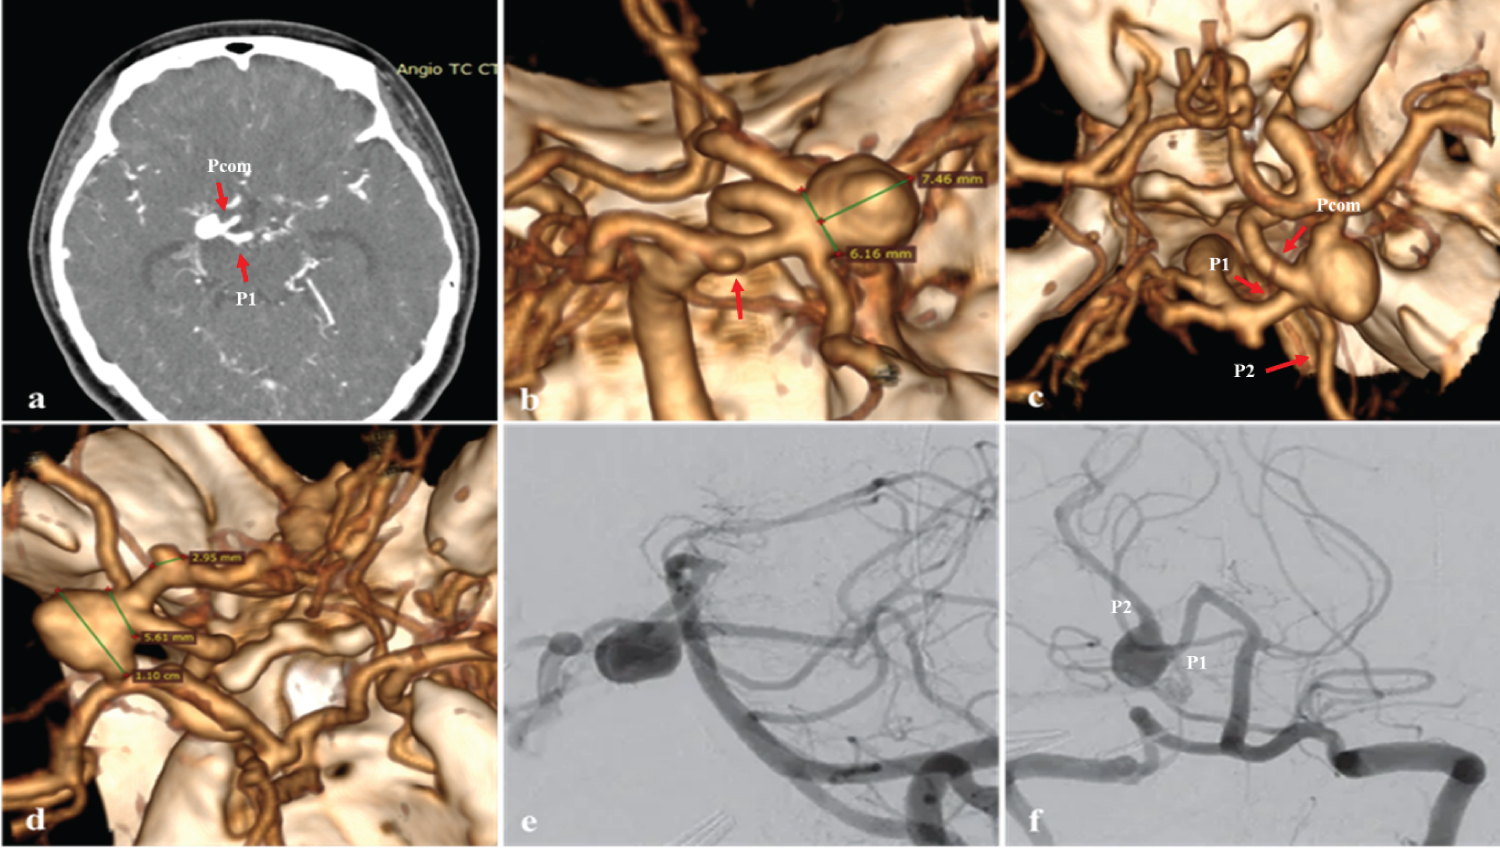

A 44-year-old woman with sudden and intense headache attended the emergency room, received analgesics and the tomography showed subarachnoid hemorrhage so she was referred to a higher resolution Hospital, studies were completed with cerebral angiography and the rupture of a saccular aneurysm in the right posterior cerebral artery of segment P1/P2 was confirmed (Figure 1). On examination we found a patient with headache of intensity 7/10, Glasgow: 15, without motor or sensory deficit, preserved cranial nerves, reactive isochoric pupils and neck stiffness (++/+++).

Figure 1: (a, b, c and d) 3D CT angiography of the arteries at the base of the skull to observe the aneurysm in the posterior cerebral artery. a) Axial section shows aneurysm at the P1/Pcom junction (red arrow);b) Posterior view, microaneurysm at the top of the basilar artery (arrow); c) Superior view, aneurysm at the P1/P2/Pcom junction, fetal posterior communicating artery (arrow); d) Right lateral view, dimensions of the aneurysm in the PCA; e, f) Digital subtraction angiography, right P1/P2 segment aneurysm. View Figure 1